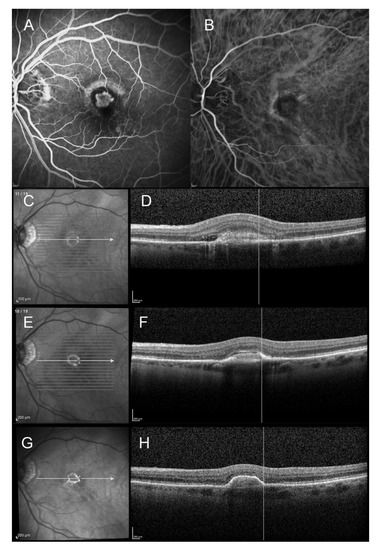

Progression from Type 2 Macular Neovascularization to Fibrovascular Pigment Epithelial Detachment

3. Results

3.3. Anatomical Outcome

4. Discussion